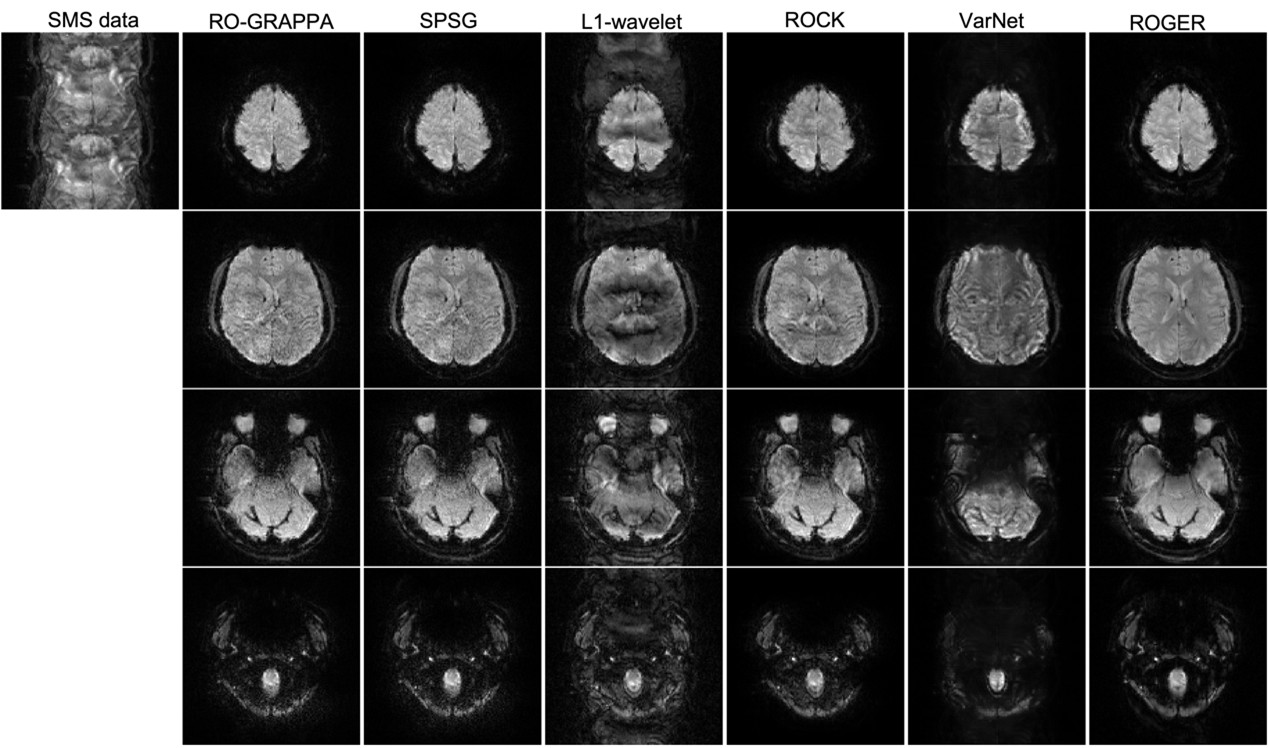

5.2 Evaluation on Unseen Brain Regions

Since the fastMRI training data does not contain slices more than 5mm below the orbital rim[zbontar2018fastmri], we used the retrospectively accelerated Huaxin dataset, covering the whole brain, including the cerebellum and brainstem, to evaluate our method on unseen anatomical regions. As indicated by the mean PSNR/SSIM values in Table 2 and the visualization in Fig. 5 at MB4R2 acceleration, our algorithm achieved the best results among all methods again, despite not being trained on the inferior brain regions. Further analysis of Table 2 revealed that ROGER’s PSNR and SSIM advantages were statistically significant (p<0.01p<0.01) compared to all other methods. Slice-level analysis presented in Fig. 6 revealed that our algorithm maintained superior performance on all slices with stable PSNR/SSIM advantages.

Refer to caption

Figure 5: Reconstructed images of retrospective SMS acceleration at MB4R2 on the Huaxin dataset with full brain coverage. Yellow numbers represent PSNR/SSIM scores. Four representative slices are presented with ground truth (GT). Our method ROGER remained robust on the brainstem area which was not present in the training set (fastMRI). Full visualizations across all slices/subjects are available in the supplementary materials.